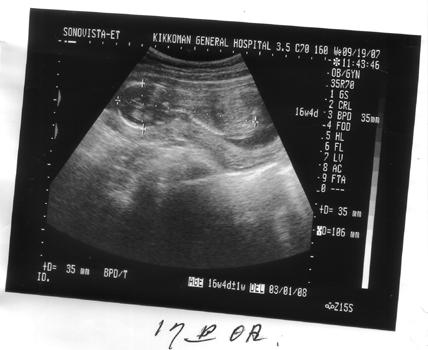

17週目です。大きくなりましたねえ

腹が出てくるわけです '‘,、'‘,、ヾ(o´∀`o)ノ '`,、'`,、

背骨がくっきりw

大きさも標準くらいらしいです。頭もw よかったw

ご主人タマも一安心です。

ご主人タマがみて一言。首は俺似か?長いんじゃない?

ええ、私、首短いんです・・・・・。大きさは足まで約15㌢。頭35㍉ 約と書いたのは、足曲がっていて、お尻までしか測れなかったので、お尻までは10.6㌢。先生に足までは?と思わず聞いてしまったw